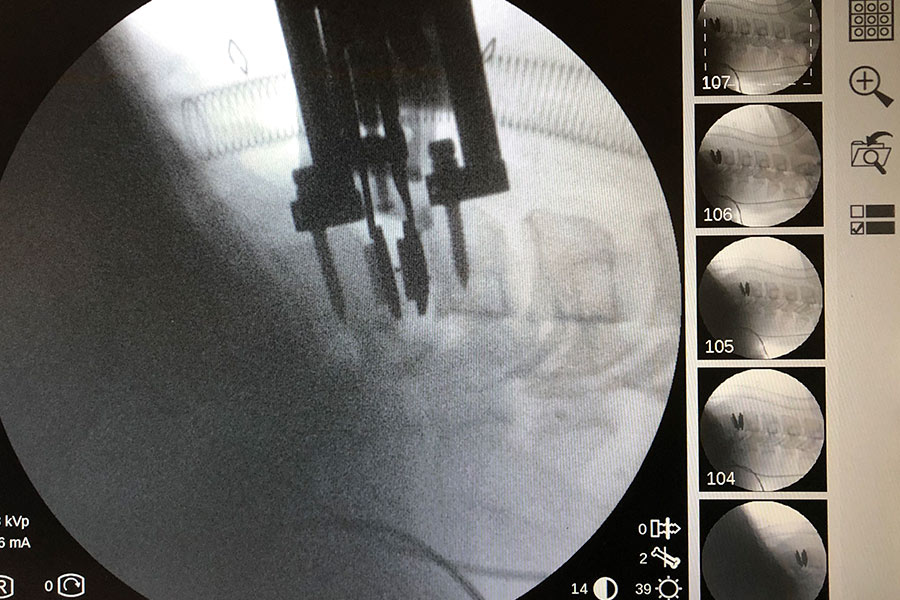

Operación

Tras varios años con tratamientos y terapias de rehabilitación, el dolor del paciente se convierte en insoportable y, por ello, decide operarse.

Se retira el implante intersomático y, tras una limpieza completa del ‘terreno’ tanto la parte intercervical como el canal, se implanta una prótesis cervical móvil.

cirugia-protesis-cervical-compleja